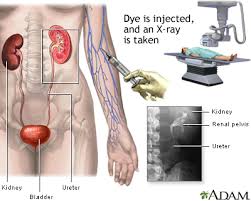

تومور سرطانی کلیه یکی از موذی ترین تومور ها هستند که در اغلب مواقع علیرغم انتشار به مناطق دیگر بدن هیچ علامت و نشانه ای ندارند و در اغلب موارد به صورت اتفاقی و در بررسی ها و چکاب کلیه با سونوگرافی و یا سی تی اسکن.

در هر ساعت کلیه های بدن انسان حدود ۷ لیتر مایع را از خون جدا می کنند این مایع را تصفیه کرده و مواد مفید و سودمند آن را به خون بازمی گردانند و مواد مضر آن را از راه میزنای به مثانه می فرستد تا دفع شوند. کجای بدنتان درد می کند مراجعه کنید آیا کلیه تان درد می کند درد کلیه در اثر عفونت کلیه یا آسیب رسیدن به آن ایجاد می شود. اما کار و وظیفه کلیه ها در بدن چیست بیا یاد بگیریم. زمانیکه کلیه ها بدرستی فعالیت کنند مواد زائد از بدن داخل ادرار ترشح می شوند همچنین کلیه ها در تنظیم سایر مواد معدنی در بدن مانند.